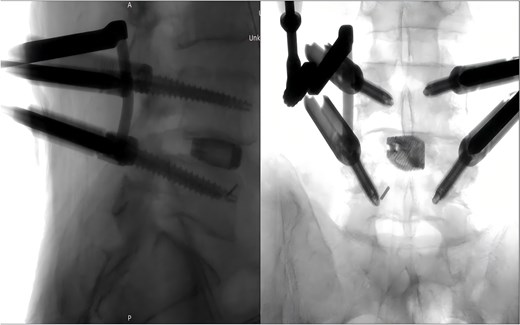

During the surgery, after sufficient decompression at the L4/L5 level and placement of the interbody fusion cage, a complication occurred during the percutaneous pedicle screw insertion. Intraoperative G-arm fluoroscopy confirmed the correct trajectory of the pedicle screw, established by the guidewire and puncture needle, and the pedicle screw was inserted along the established pathway (Fig. 2). However, after removing the guidewire, fluoroscopic imaging revealed that a portion of the guidewire had broken near the anterior margin of the left L5 pedicle screw (Fig. 3). The fracture likely occurred during screw insertion or tightening, which subsequently displaced the broken guidewire toward the anterior vertebral margin. Given the proximity of the fractured guide wire to the anterior vertebral margin, along with the risks of future migration causing injury to adjacent tissues or vessels, as well as the potential for local infection or pain, the decision was made to remove the fractured guidewire after obtaining informed consent from the patient’s legal representative.

Intraoperative fluoroscopic confirmation of guidewire breakage.